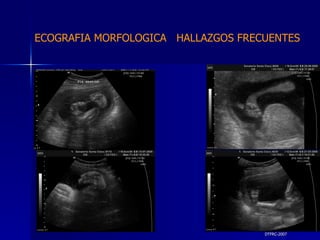

DTFRC-2007 ECOGRAFIA MORFOLOGICA  HALLAZGOS FRECUENTES   MATERIAL Y METODO ES UN ESTUDIO DESCRIPTIVO, RETROSPECTIVO  DE ESTUDIO ECOGRA FICOS REALIZADOS ENTRE MARZO 07 A MARZO 08 EQUIPO DE ALTA RESOLUCION   VOLUSON 730 PRO  MEDISON SA 8000 live MEDISON SA 8000SE CRITERIO DE INCLUSION:   POBLACION GENERAL    GESTACIONES  20 a 24 SEMANAS   UNIVERSO  N 211

DTFRC-2007 ECOGRAFIA MORFOLOGICA  HALLAZGOS FRECUENTES   Sistema Nervioso Central  8  Cardiovascular  0 Genitourinario  6 Musculos Esqueleticos  2 Gastrointestinales  2  Otros  12  Total  30   NUMEROS DE ANOMALIAS POR SISTEMA n N  211

DTFRC-2007 ECOGRAFIA MORFOLOGICA  HALLAZGOS FRECUENTES   SISTEMA NERVIOSO CENTRAL TOTAL  8  26 % 1 HIDROCEFALIA 2 VENTRICULO MEGALIA 4 QUISTE DE PLEXO COROIDEO 1 ANENCEFALIA

DTFRC-2007 ECOGRAFIA MORFOLOGICA  HALLAZGOS FRECUENTES   GENITOURINARIA DISPLASIA RENAL MULTIQUISTICA  3 HIDRONEFROSIS  2 QUISTE DE OVARIO FETAL  1 SISTEMA DIGESTIVO DILATACION INTESTINAL  2  SISTEMA ESQUELETICO   PIE BOT  2  20 % 6 % 6 %

DTFRC-2007 ECOGRAFIA MORFOLOGICA  HALLAZGOS FRECUENTES   OTROS HIGROMA QUISTICO  2 ENFERMEDAD ADENOMATOSA PULMONAR  1 ARTERIA UMBILICAL UNICA  2 HIDROPS FETAL NO INMUNE  1 QUISTE DE CORDON UMBILICAL  1 ALTERACION DE LIQUIDO ANMIOTICO  2 SINDROME TRAFUSIONAL FETO FETAL 1 LABIO LEPORINO  2 TOTAL  12  42 %